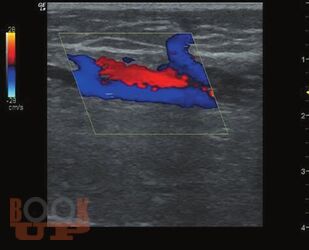

Ультразвуковое исследование вен нижних конечностей: анатомия, рефлюксы, тромбозы и хирургические подходы

Когда врач решает освоить ультразвуковое исследование вен нижних конечностей, первое, с чем он сталкивается - вен там очень много и в них легко запутаться. Кроме этого, в венах есть правильное направление течения крови, а есть неправильное - рефлюкс, и его нужно уметь правильно определять в нужных местах. Кроме рефлюксов, в венах встречается более опасное заболевание - тромбоз. Очень важно понять, где ситуация критическая и с найденным тромбом нужно срочно что-то делать, а где - ничего страшного, больному можно улыбнуться и сказать: «пройдет само». Кроме этого, в венах (в отличие от артерий) очень выражена индивидуальная изменчивость, нет понятия «нормальных» размеров и «гемодинамически значимого стеноза».